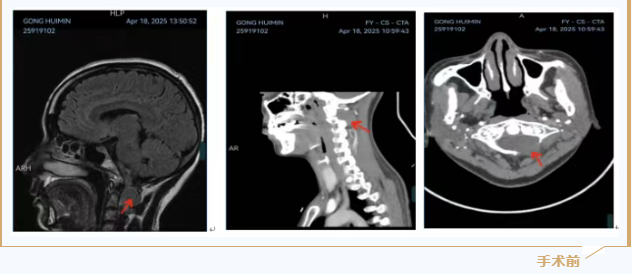

近半年来,45岁的龚女士颈肩持续胀痛,且不适感逐渐加剧,近期左手变得无力,紧急到贵阳市第一人民医院就医。检查结果令人震惊:一颗肿瘤,长在了颈椎最顶端、最要害的“生命禁区”——寰枢椎位置。

贵阳市第一人民医院主刀医生、骨科二病区连学辉主任解释道:“这个区域的脊髓,是大脑连接四肢和呼吸心跳的‘神经中枢总缆’,肿瘤已经将脊髓压得变形,再发展下去,患者随时可能高位截瘫,甚至呼吸停止。”